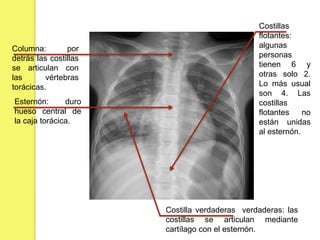

La caja torácica

 En el pecho tenemos 12 pares de costillas

Columna: por

detrás las costillas

se articulan con

las vértebras

torácicas.

Esternón: duro

hueso central de

la caja torácica.

Costillas

flotantes:

algunas

personas

tienen 6 y

otras solo 2.

Lo más usual

son 4. Las

flotantes no

están unidas

al esternón.

Costilla verdaderas verdaderas: las

costillas se articulan mediante

cartílago con el esternón.